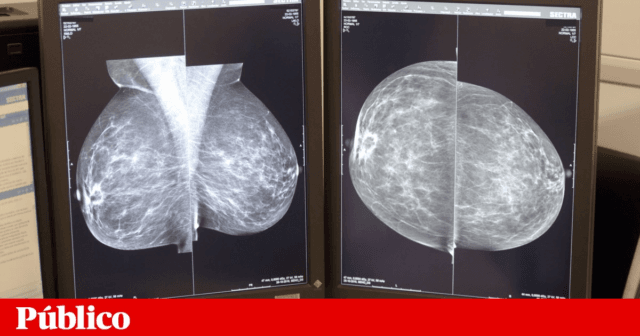

Início Atualidade Inteligência artificial identifica risco de cancro na mama com bastante antecedência NotíciasAtualidade Inteligência artificial identifica risco de cancro na mama com bastante antecedência Por forumenfermagem - 1 Fevereiro, 2025 291 0 FacebookTwitterWhatsAppLinkedinTelegram Dados da Organização Mundial da Saúde indicam que 670 mil mulheres morreram em 2022 devido ao cancro da mama, o tipo de tumor maligno mais comum nas mulheres na grande maioria dos países. Leia na íntegra em Publico.pt